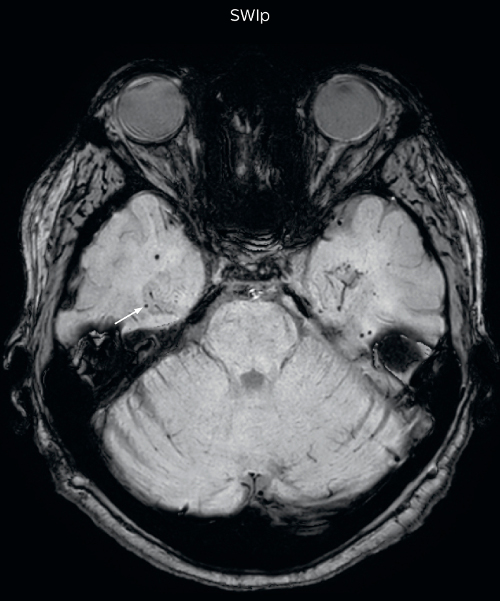

Hemosiderin foci in brain

Gradient echo imaging and SWIp are compared in a patient with radiation-induced foci of hemosiderin deposition. A greater number of small foci is seen on the SWIp image. Ingenia 3.0T